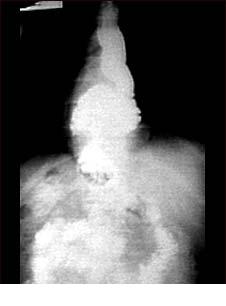

Hernia hiatala